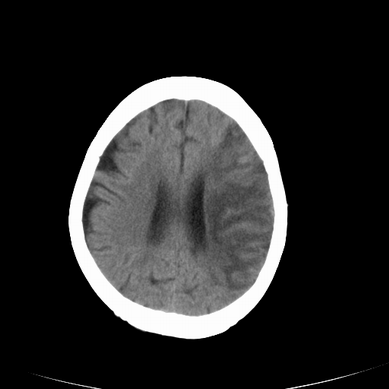

以下是引用jsgdoctor在2008-7-16 23:11:00的发言:[br]左侧大脑中动脉供血区脑梗塞